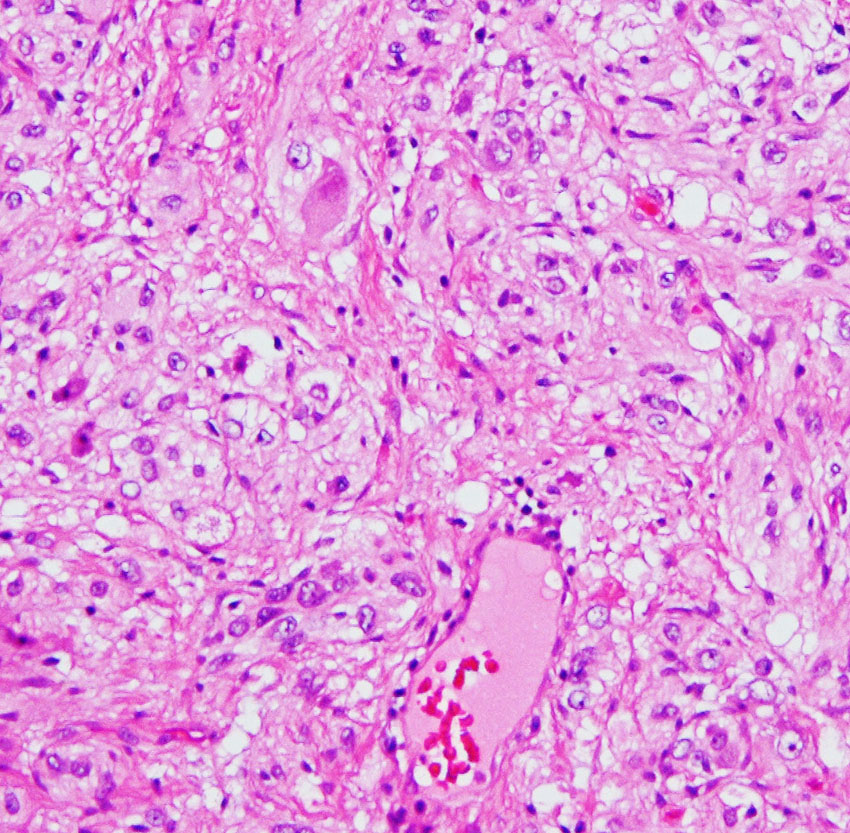

小児の良性の神経節膠腫 ganglioglioma グレード1(真の腫瘍)

7才の時に音読でつかえるようになり,眼で何かを追っているような欠伸発作(左側頭葉てんかん)を繰り返すようになり,強直間代発作を生じて腫瘍が発見されました。下側頭回底面の皮質に発生した境界明瞭な腫瘍であり,周囲に脳浮腫を伴っています。T2強調画像で線維成分の多い硬い部分は低信号に,軟らかい部分はやや高信号となり,ガドリニウムでheterogenousに増強されます。グレード1の神経節膠腫としては非典型的な画像所見で術前診断は難しいもので,PXA pleomorphic xanthoastrocytoma も疑いました。もちろん治療としては開頭手術での全摘出です。術後に発作は消失しています。

構成要素はGFAP陽性の膠細胞が多く認められます。神経細胞様形態の細胞 ganglion cellではNeuN(+), CGA (+) synaptophisin (++), neurofilament (+)です。大型で腫大した核を有して核内封入体構造を有する好酸性もしくは淡明な細胞質を有する細胞が増殖してPXAを考えさせる部分像もありました。granular bodyも認められて,右の写真のように膠原線維の増生が目立つ部分もあります。これは表面の非常に硬い線維性の腫瘍部分です。MIB-1 indexは4%とやや高い値です。BRAF v600Eの変異が認められました。